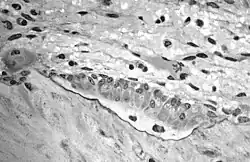

Остеобла́сты (от др.-греч. ὀστέον — «кость» + др.-греч. βλάστη — «росток, отпрыск, побег») — молодые клетки костной ткани (диаметром 15-20 мкм), которые синтезируют межклеточное вещество — матрикс. По мере накопления межклеточного вещества остеобласты замуровываются в нём и становятся остеоцитами. Остеобласты богаты элементами зернистой эндоплазматической сети, рибосомами, имеют хорошо развитый комплекс Гольджи. Их многочисленные отростки контактируют между собой и с отростками остеоцитов. Вспомогательной функцией остеобластов является участие в процессе отложения солей кальция в межклеточном веществе (кальцификации матрикса) благодаря высокому содержанию щелочной фосфатазы, что свидетельствует о высокой синтетической активности остеобластов. При этом происходит образование полостей (лакун), в которых они и залегают, превращаясь в остеоциты.

В сформировавшейся кости остеобласты встречаются только в местах разрушения и восстановления костной ткани, тогда как в развивающейся кости они непрерывным слоем покрывают почти всю поверхность формирующейся костной балки. Остеобласты располагаются вокруг первичных костных перекладин, образованных коллагеновыми волокнами. Оказавшись между ними, многие остеобласты замуровываются в межклеточном веществе и становятся остеоцитами. Так возникает костная ткань.